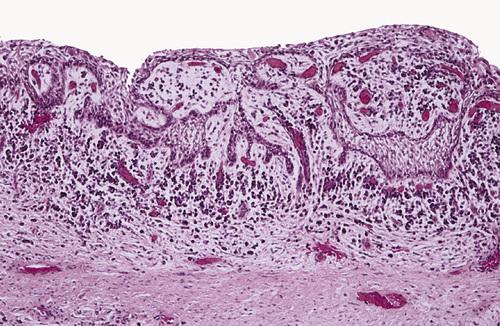

This inflamed cyst shows a thick epithelial lining with hyperplastic rete ridges and diffuse chronic inflammatory infiltrate.

dentigerous cyst, inflammed